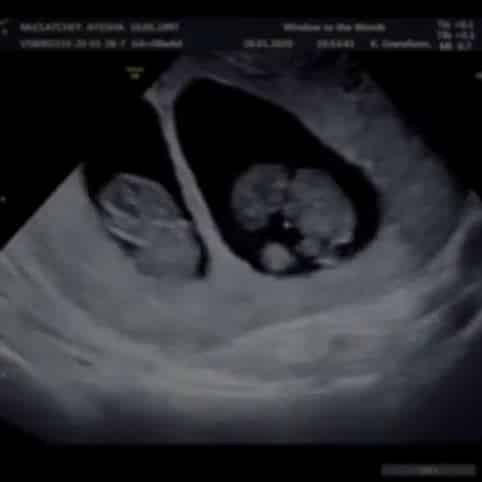

Last Tuesday marked a year ago since our first scan, the first time we ever saw our babies! We waited anxiously, my sickness heightened, we had hoped and prayed to see a healthy heartbeat.

I was drawn to a collage on the wall of then and now pictures. It was filled with scan photos and pictures a year on of babies who had safely entered the world. One picture clocked my attention, the couple had twins. I mentioned it to Dan and said to him to look, they had chosen 1 of our favourite baby names which was quite uncommon so it just made me smile. His response still makes me laugh to this day, he laughed and said, twins though babe, think that would be my worst nightmare. Well darling, your nightmare was quickly upon us.

Have to say despite his shock and me beaming with happiness and tears, neither of us would swap what we have now for the world. We actually say to ourselves, imagine how different it would be with 1 baby!! Sure we’d get more sleep and probably more time to ourselves, but watching the twins bond together from birth through till now at almost 6 months old has been utterly magical.